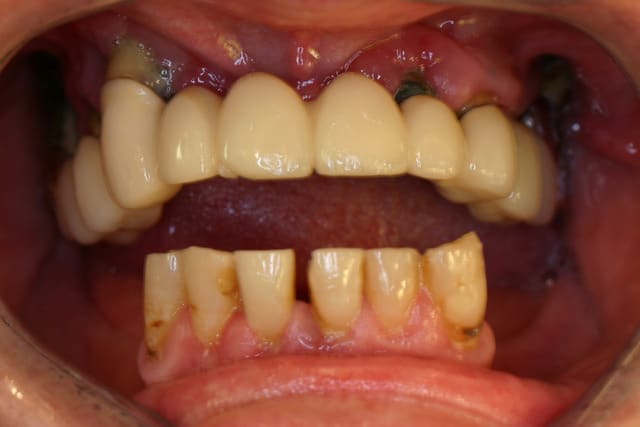

1.Bon... situation pré-extractionelle ( Je crois qu il faillait vraiment extraire )

2. Complet à essai en bouche après extraction et PRFs ds tous les alvéoles puis 3 séances d ostéotensions à venir pour le maxillaire

3. Vue sur articu